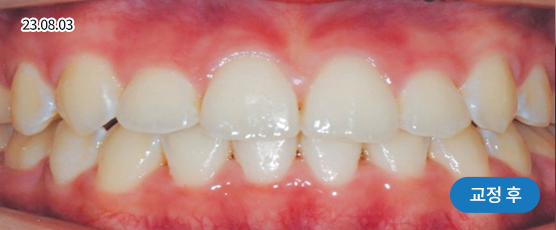

* 본 사진은 동일 조건에서 촬영되었으며, 환자 본인의 동의를 얻어 게재되었습니다.